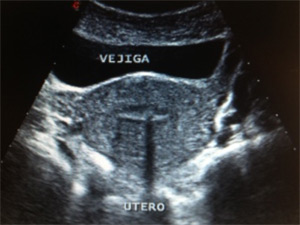

Realizaremos una ecografía transvaginal con el objetivo de valorar la morfología del útero y ovarios. Con una sencilla ecografía podemos detectar tanto malformaciones uterinas,presencia de miomas o pólipos endometriales y descartar la presencia de tumoraciones ováricas.

Ecografía de útero normal